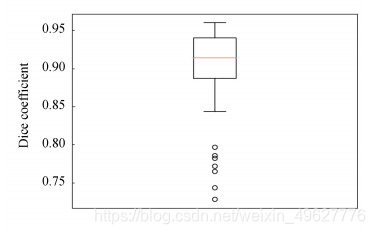

图 10 脑肿瘤测试集Dice分布

从图 10所展示的脑肿瘤测试集57例病例样本的Dice指标分布可知,与图 8(b)相比,结合了实例归一化的脑肿瘤检测结果最低的Dice值也可达到0.41,较3.2.1节的实验结果最低Dice值提升了约0.4,也仅有两个严重的远离集群点.